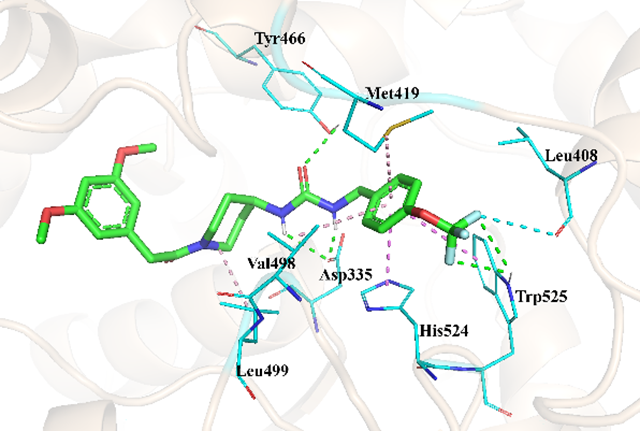

通過X射線晶體學解析了DJ-89與sEH復合物的共晶結構(PDB 編號: 9KPI),研究發現其苯乙酰哌啶骨架與sEH酶活性腔形成多重相互作用:脲基與Asp335、Tyr466形成氫鍵,增強結合能力;三氟甲氧基芐基通過π-π作用與His524結合,增強親和力;哌啶環的構象約束減少分子柔性,增加了額外的相互作用力。相較于傳統sEH抑制劑,DJ-89的獨特結構使其在結合強度上實現提升。

圖4 化合物77(DJ-89)與sEH的結合模式